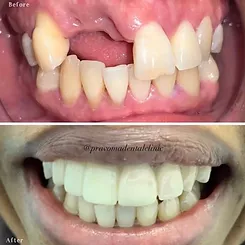

Dental veneers are wafer-thin, custom-made shells of tooth-coloured materials designed to cover the front surface of teeth to improve your appearance. Veneers placed on the surface of affected teeth improve badly stained, shaped or crooked teeth. Comprising thin pieces of porcelain or plastic cemented over the front of your teeth, they also allow patients to change the colour or shape. Veneers are used on teeth with uneven surfaces or teeth that are chipped, discoloured, oddly shaped, unevenly spaced or crooked. Little or no anaesthesia is needed.

Veneers have a longer life expectancy & colour stability than bonding and resist staining from coffee, tea or cigarette smoking. Veneers can mask undesirable defects (teeth stained by tetracycline, by an injury or as a result of a root-canal procedure) and are ideal for masking discoloured fillings in front teeth. Veneers are also an excellent choice for patients with gaps between front teeth or those that are chipped or worn may. The process entails diagnosis and treatment planning, preparation, and bonding. And the result: a brand new, confident smile!